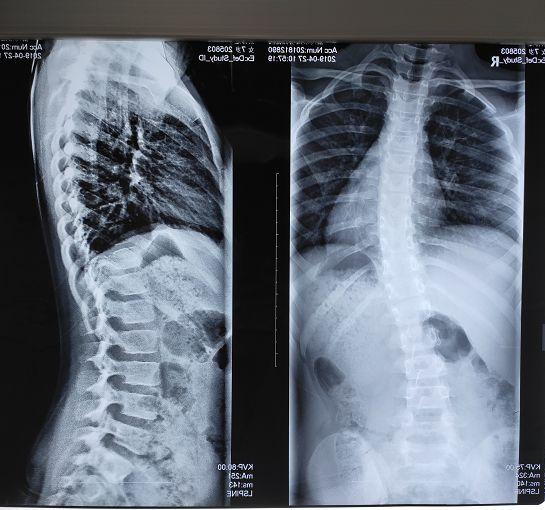

腰椎侧弯图片 x光

腰椎侧弯图片 x光,腰椎侧弯图片x光

儿童健康儿童脊柱侧弯暑假迎来就诊高峰67年龄最小患者仅4岁医生

下面这张x光片可以表示脊椎侧弯,从后面看腰椎棘突的连线像写一个「c